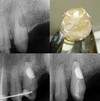

Kanal Tedavisi Tekrarı

Apikal Cerrahi

Turk Endod J. 2016 :Non-Surgical Endodontic Retreatment and follow-up of an Endo – Perio Lesion: A Case Report